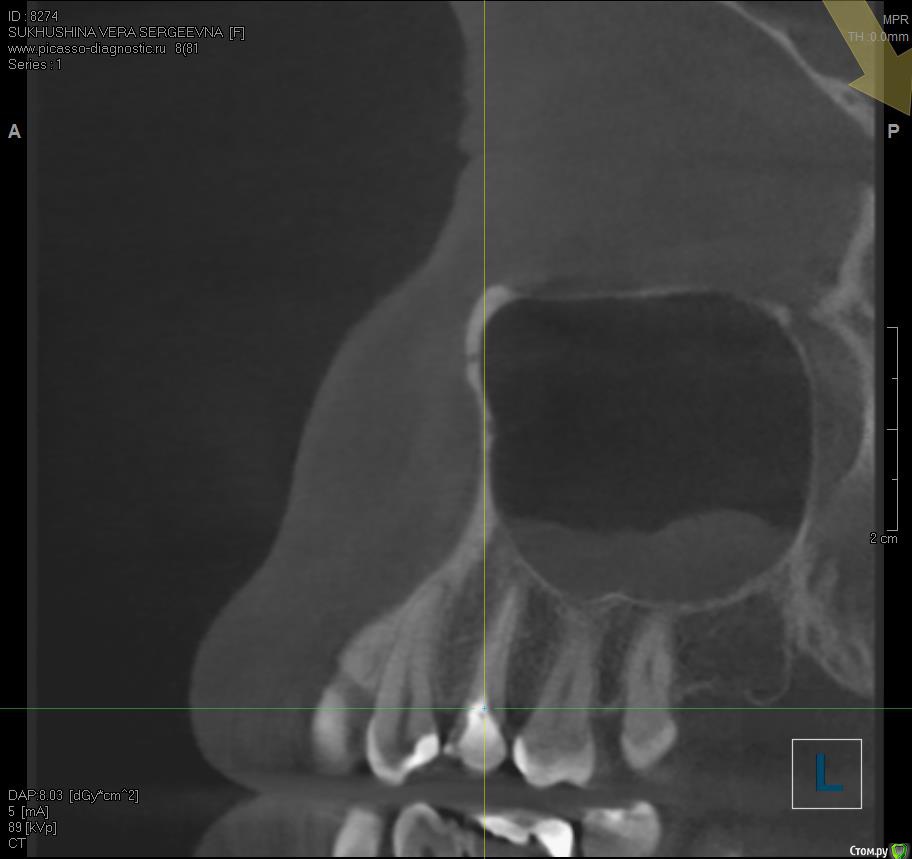

Verasss Опубликовано 8 октября, 2016 Автор Поделиться Опубликовано 8 октября, 2016 КТ от 08.09. Извините, что в таком виде, надо менять ОЗУ. Ссылка на комментарий

DmitrySH Опубликовано 8 октября, 2016 Поделиться Опубликовано 8 октября, 2016 В таком виде КТ малоинформативно. Но гайморита нет. Ссылка на комментарий

Verasss Опубликовано 28 октября, 2016 Автор Поделиться Опубликовано 28 октября, 2016 Добрый вечер! Ещё раз попытаюсь прикрепить скриншоты КТ от сентября. Если качество совсем не устраивает, подскажите, пожалуйста, какие сделать снимки?К сожалению, программа не позволяет вывести снимки на полный экран и заскриншотить в более хорошем качестве. Ссылка на комментарий

Verasss Опубликовано 23 ноября, 2016 Автор Поделиться Опубликовано 23 ноября, 2016 Сделала ещё 1 кт, спустя почти 2,5 месяца после первого. Посмотрите, пожалуйста, есть ли изменения? Напомню, что пункцию гайморовой мне сделали. Ссылка на комментарий